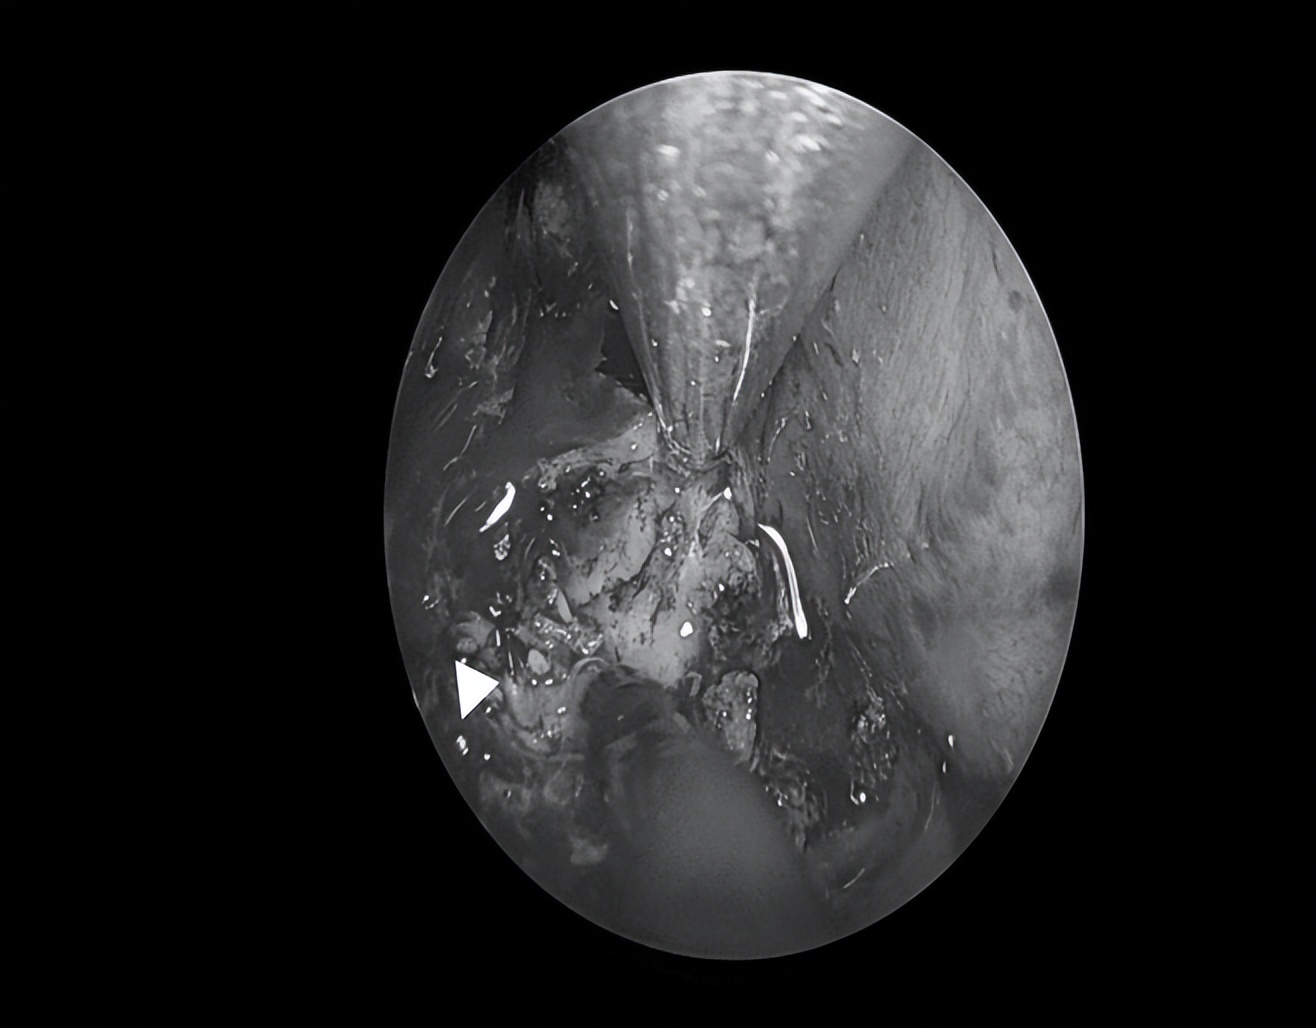

显露中颅窝底肿瘤

沿肿瘤包膜磨除肿瘤周边骨质,充分暴露肿瘤边界

切开肿瘤包膜后,可见大量豆渣样物

清除豆渣样物,显露岩骨段颈内动脉

清除囊内病变后可见中颅窝底塌陷

(星号标示处)

切除部分囊壁,清除囊内病变,充分向鼻腔开放引流